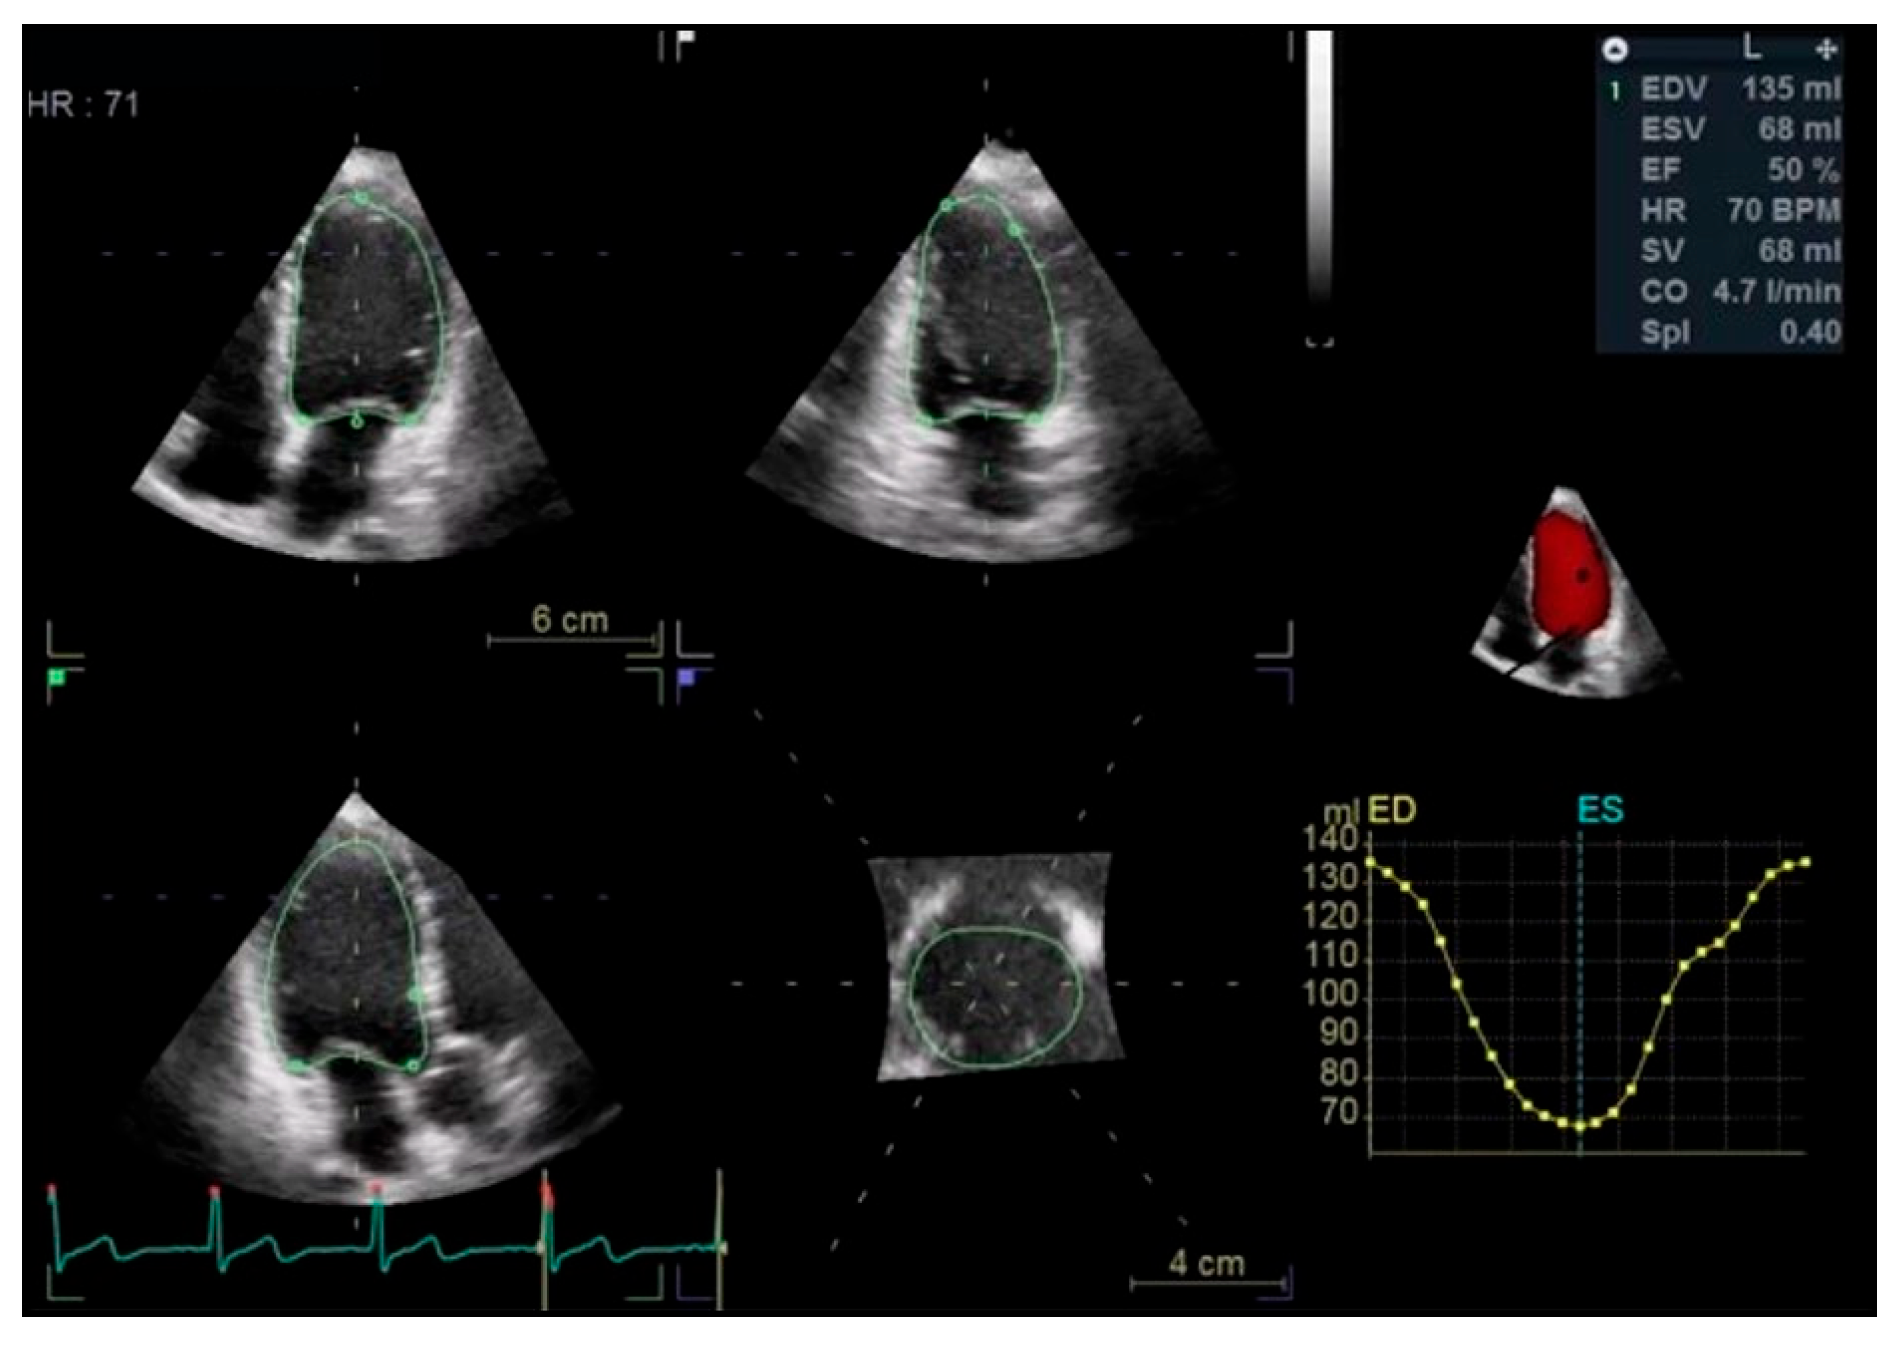

Left Ventricular Systolic Function

- CAIANI, E. Improved Semiautomated Quantification of Left Ventricular Volumes and Ejection Fraction Using 3-Dimensional Echocardiography with a Full Matrix-Array Transducer: Comparison with Magnetic Resonance Imaging. J. Am. Soc. Echocardiogr. 2005, 18, 779–788. [Google Scholar] [CrossRef] [PubMed]

- Mor-Avi, V.; Jenkins, C.; Kühl, H.P.; Nesser, H.-J.; Marwick, T.; Franke, A.; Ebner, C.; Freed, B.H.; Steringer-Mascherbauer, R.; Pollard, H.; et al. Real-Time 3-Dimensional Echocardiographic Quantification of Left Ventricular Volumes. JACC Cardiovasc. Imaging 2008, 1, 413–423. [Google Scholar] [CrossRef] [PubMed]

- Dorosz, J.L.; Lezotte, D.C.; Weitzenkamp, D.A.; Allen, L.A.; Salcedo, E.E. Performance of 3-Dimensional Echocardiography in Measuring Left Ventricular Volumes and Ejection Fraction: A Systematic Review and Meta-Analysis. J. Am. Coll. Cardiol. 2012, 59, 1799–1808. [Google Scholar] [CrossRef]

- Muraru, D.; Badano, L.P.; Peluso, D.; Dal Bianco, L.; Casablanca, S.; Kocabay, G.; Zoppellaro, G.; Iliceto, S. Comprehensive Analysis of Left Ventricular Geometry and Function by Three-Dimensional Echocardiography in Healthy Adults. J. Am. Soc. Echocardiogr. 2013, 26, 618–628. [Google Scholar] [CrossRef] [PubMed]